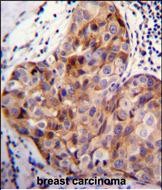

SCUBE2 Antibody (Center N266) (Cat. #P34924)immunohistochemistry analysis in formalin fixed and paraffin embedded human breast carcinoma followed by peroxidase conjugation of the secondary antibody and DAB staining.This data demonstrates the use of SCUBE2 Antibody (Center N266) for immunohistochemistry. Clinical relevance has not been evaluated.